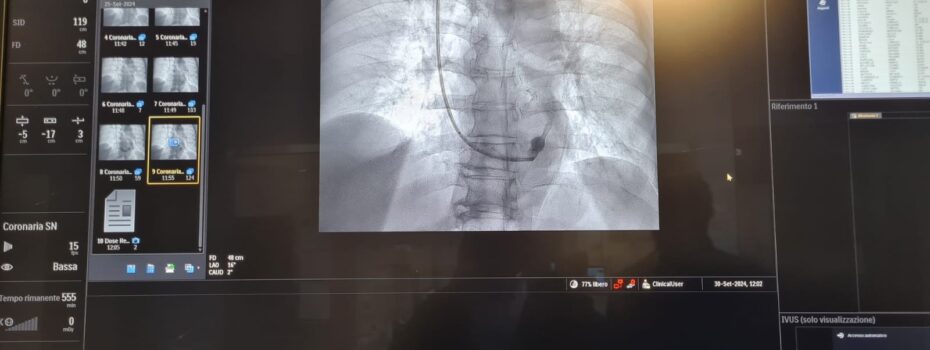

Un intervento chirurgico programmato con il supporto dell’intelligenza artificiale è stato eseguito con successo all’ospedale Ospedale Di Venere di Bari. Lo ha reso noto la Asl Bari, spiegando che si tratta del primo intervento di riparazione endovascolare di aneurisma dell’aorta addominale pianificato attraverso sistemi di analisi predittiva e tecnologia “Digital Twin”, il cosiddetto “gemello digitale”. […]